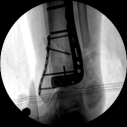

2.CO接骨機器人持續(xù)牽引維持復(fù)位,選擇前外側(cè)切口對前外側(cè)骨塊進(jìn)行撬撥復(fù)位,并用克氏針進(jìn)行臨時固定。C臂透視復(fù)位滿意,放置兩塊鋼板進(jìn)行固定。

3.在脛骨近端穿入一根克氏針,連接CO外固定架進(jìn)行固定,并外踝處穿入一根克氏針進(jìn)行固定。C臂透視位置滿意,縫合結(jié)束手術(shù)。